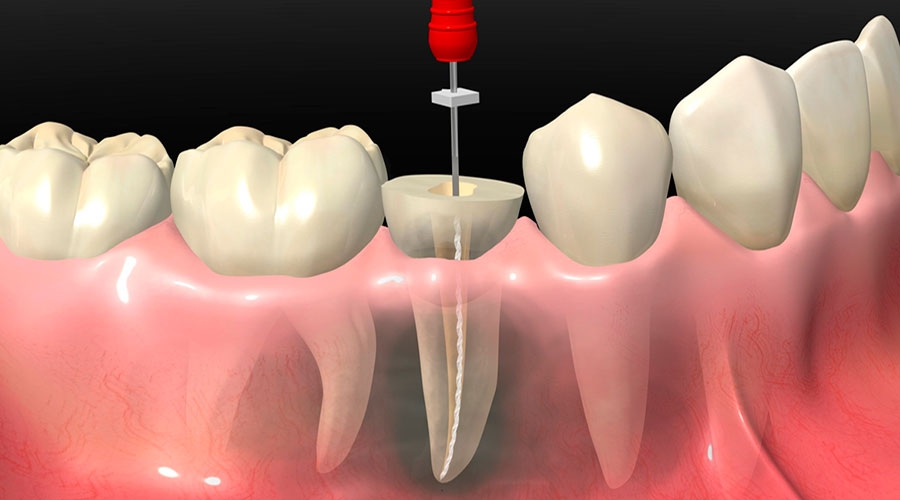

Para dentes com grande destruição da estrutura, fraturas, hipersensibilidade ou exposição da polpa, onde há a possibilidade de serem utilizados em uma reabilitação protética.

Tratamento de canal